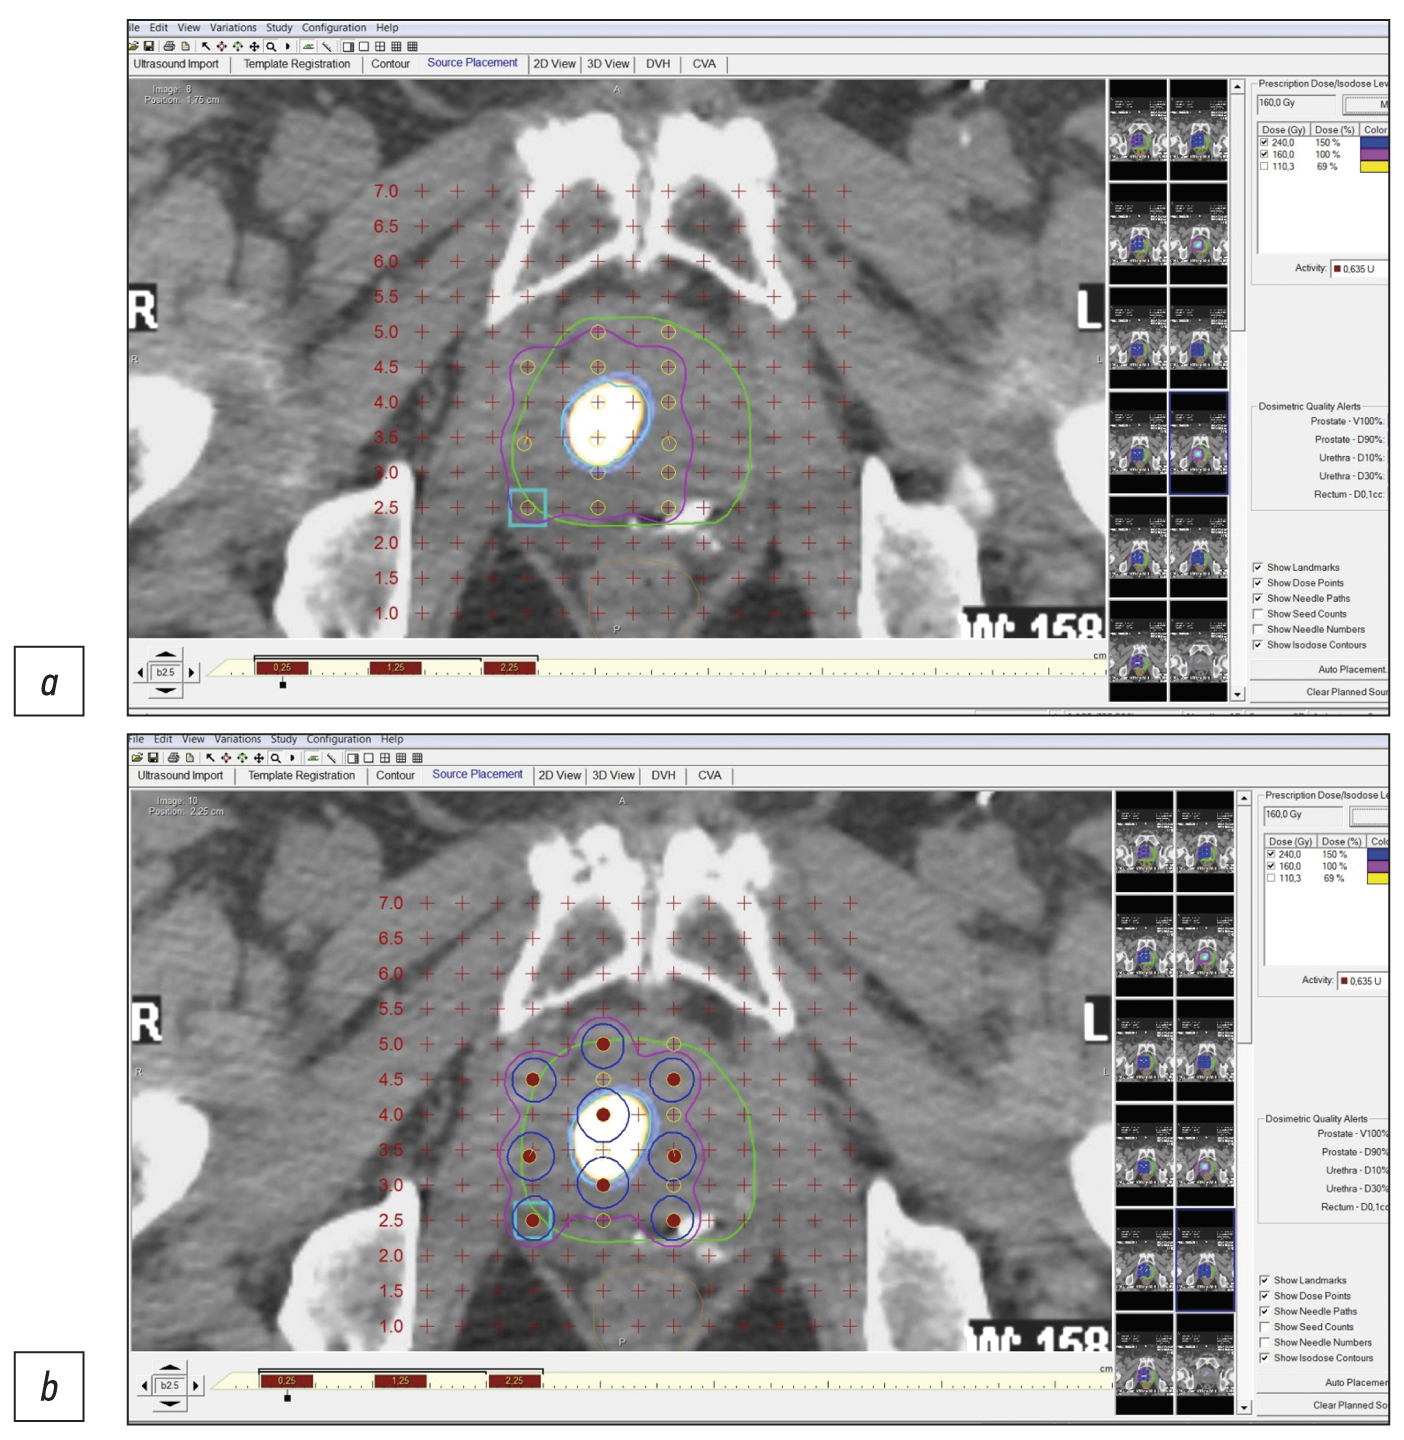

Precision low-dose brachytherapy of prostate cancer under PSMA-receptor molecular visualization

Brachytherapy with implantation of micro sources based on isotope 125I is a preferred treatment for localized prostate cancer without signs of germination of the gland capsule and in the absence of signs of metastases (stage cT1-T23aN0M0). Structural imaging methods (ultrasound, computed tomography, and magnetic resonance imaging) do not have high specificity in the differential diagnosis of prostate cancer. Hybrid technologies of radiation imaging (single-photon emission computed tomography/computed tomography, positron emission tomography/computed tomography, and positron emission tomography/magnetic resonance imaging) combine the advantages of high sensitivity of cross-sectional structural imaging methods (computed tomography and magnetic resonance imaging) and high specificity of molecular imaging methods (single-photon emission computed tomography and positron emission tomography) with tumorotropic radiopharmaceuticals. In this original clinical study, based on seven observations of localized prostate cancer (Gleason 6–7), it was shown that the precision of low-dose brachytherapy using 125I micro sources of localized prostate carcinomas, along with targeted biopsy, can be increased using hybrid methods of PSMA-receptor molecular imaging (single-photon emission computed tomography/ computed tomography, positron emission tomography/ computed tomography). The single-photon emission computed tomography/ computed tomography method is more accessible than positron emission tomography/ computed tomography. Moreover, when coupled with cold kits (HYNIC-PSMA), it allows research within any radioisotope diagnostics laboratory equipped with single-photon emission computed tomography/ computed tomography. The innovative technology of PSMA-navigation biopsy and brachytherapy, under the control of hybrid molecular imaging, can be used in primary and recurrent cases of localized prostate cancer, increases the accuracy and reduces the traumatic nature of procedures, and increases the medical and economic efficiency of low-dose brachytherapy with 125I micro sources. Further research is needed to improve the technology and evaluate its long-term results.